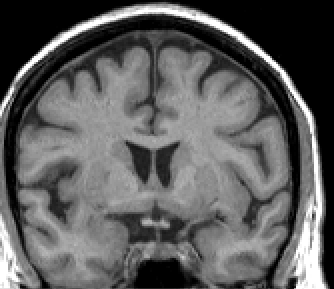

Turn the automatically generated outline into a contour by un-extracting it with 'W'. Then draw 'd' and erase 'q' to make any necessary corrections, and finally save the outline. The basic idea is to obtain an outline that includes all CSF and excludes bone. Compact bone is very dark but the marrow inside the bone will be anywhere from gray to very bright.

In the middle portion of the ICC, continue extracting all Cortex and CSF, but be aware of and exclude all veins, cranial nerve roots, and bony protuberances that appear, particularly as the brainstem appears.